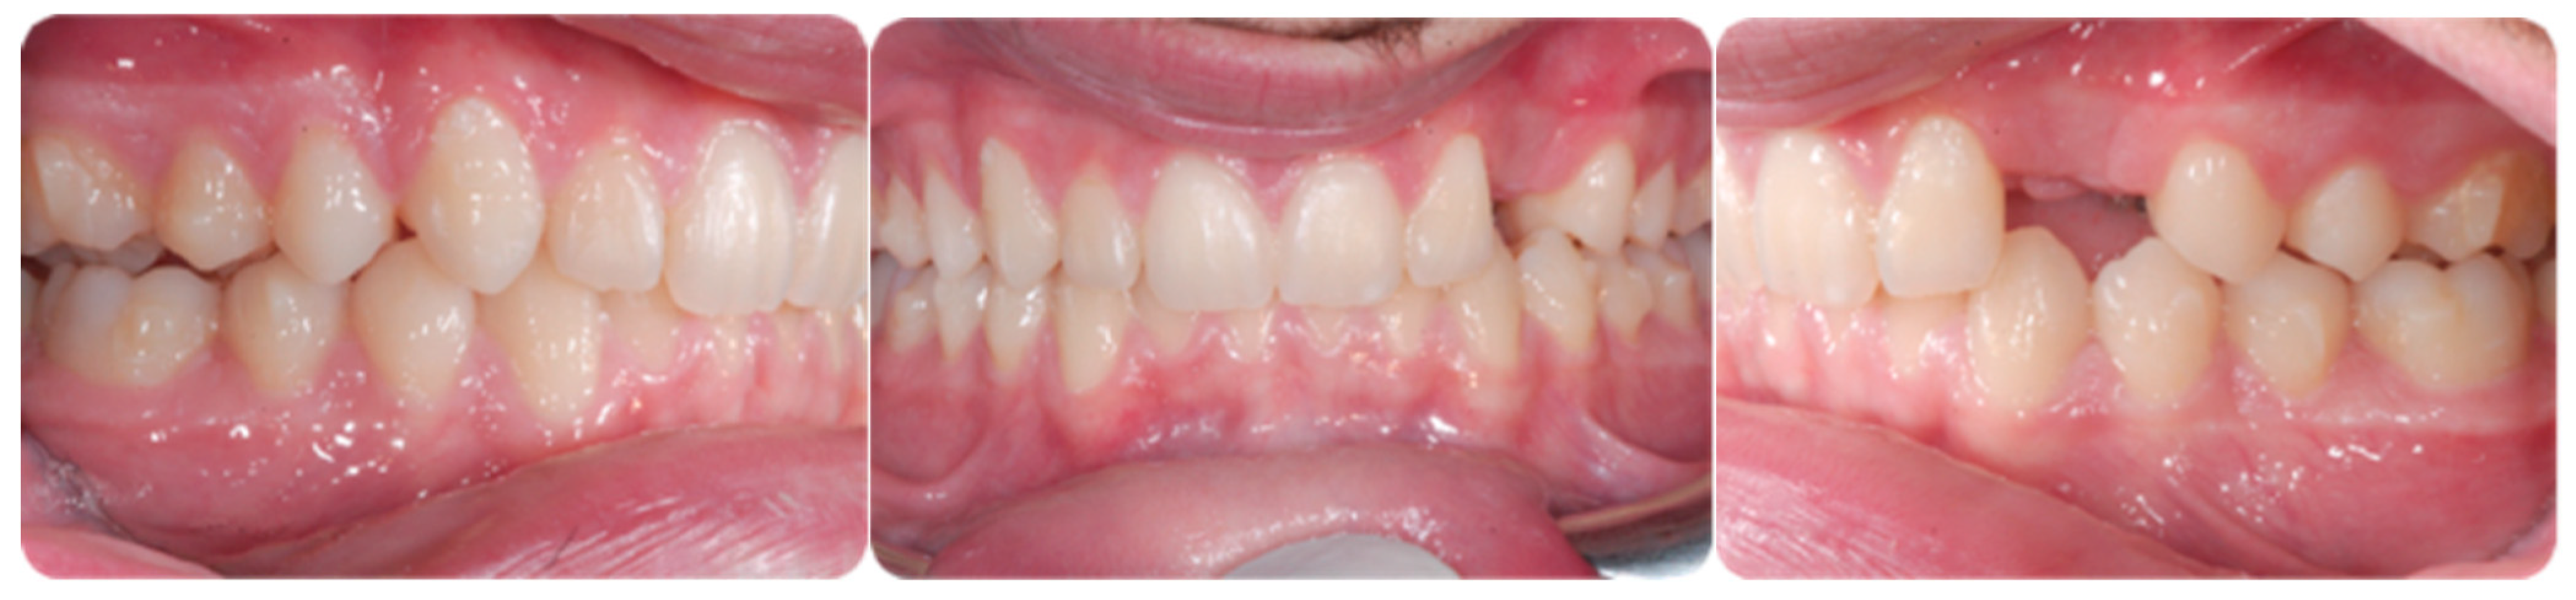

An adult female patient, 43 years old, with Class I occlusion on both sides and with a slight deep bite, light crowding, a persistent deciduous canine no. 63, and a horizontally impacted canine with the crown tip close to the lateral incisors and the tip of the root protruding beyond the buccal bone in the 2.3 area is presented in Figure 9 and Figure 10.

Figure 9.

Class I occlusion on both sides with a slight deep bite, light crowding, a persistent deciduous canine no. 63, and a horizontally impacted canine with the tip of the crown close to the lateral incisors and the tip of the root protruding beyond the buccal bone in the 2.3 area.

Figure 10.

CBCT pictures of the patient. Since the patient was subjected to periodic radiographic control as she was a cancer survivor, the decision was to do a CBCT to receive all the informations useful for the deimpaction treatment and avoid conventional orthodontic X-rays like panoramic and lateral X-rays.